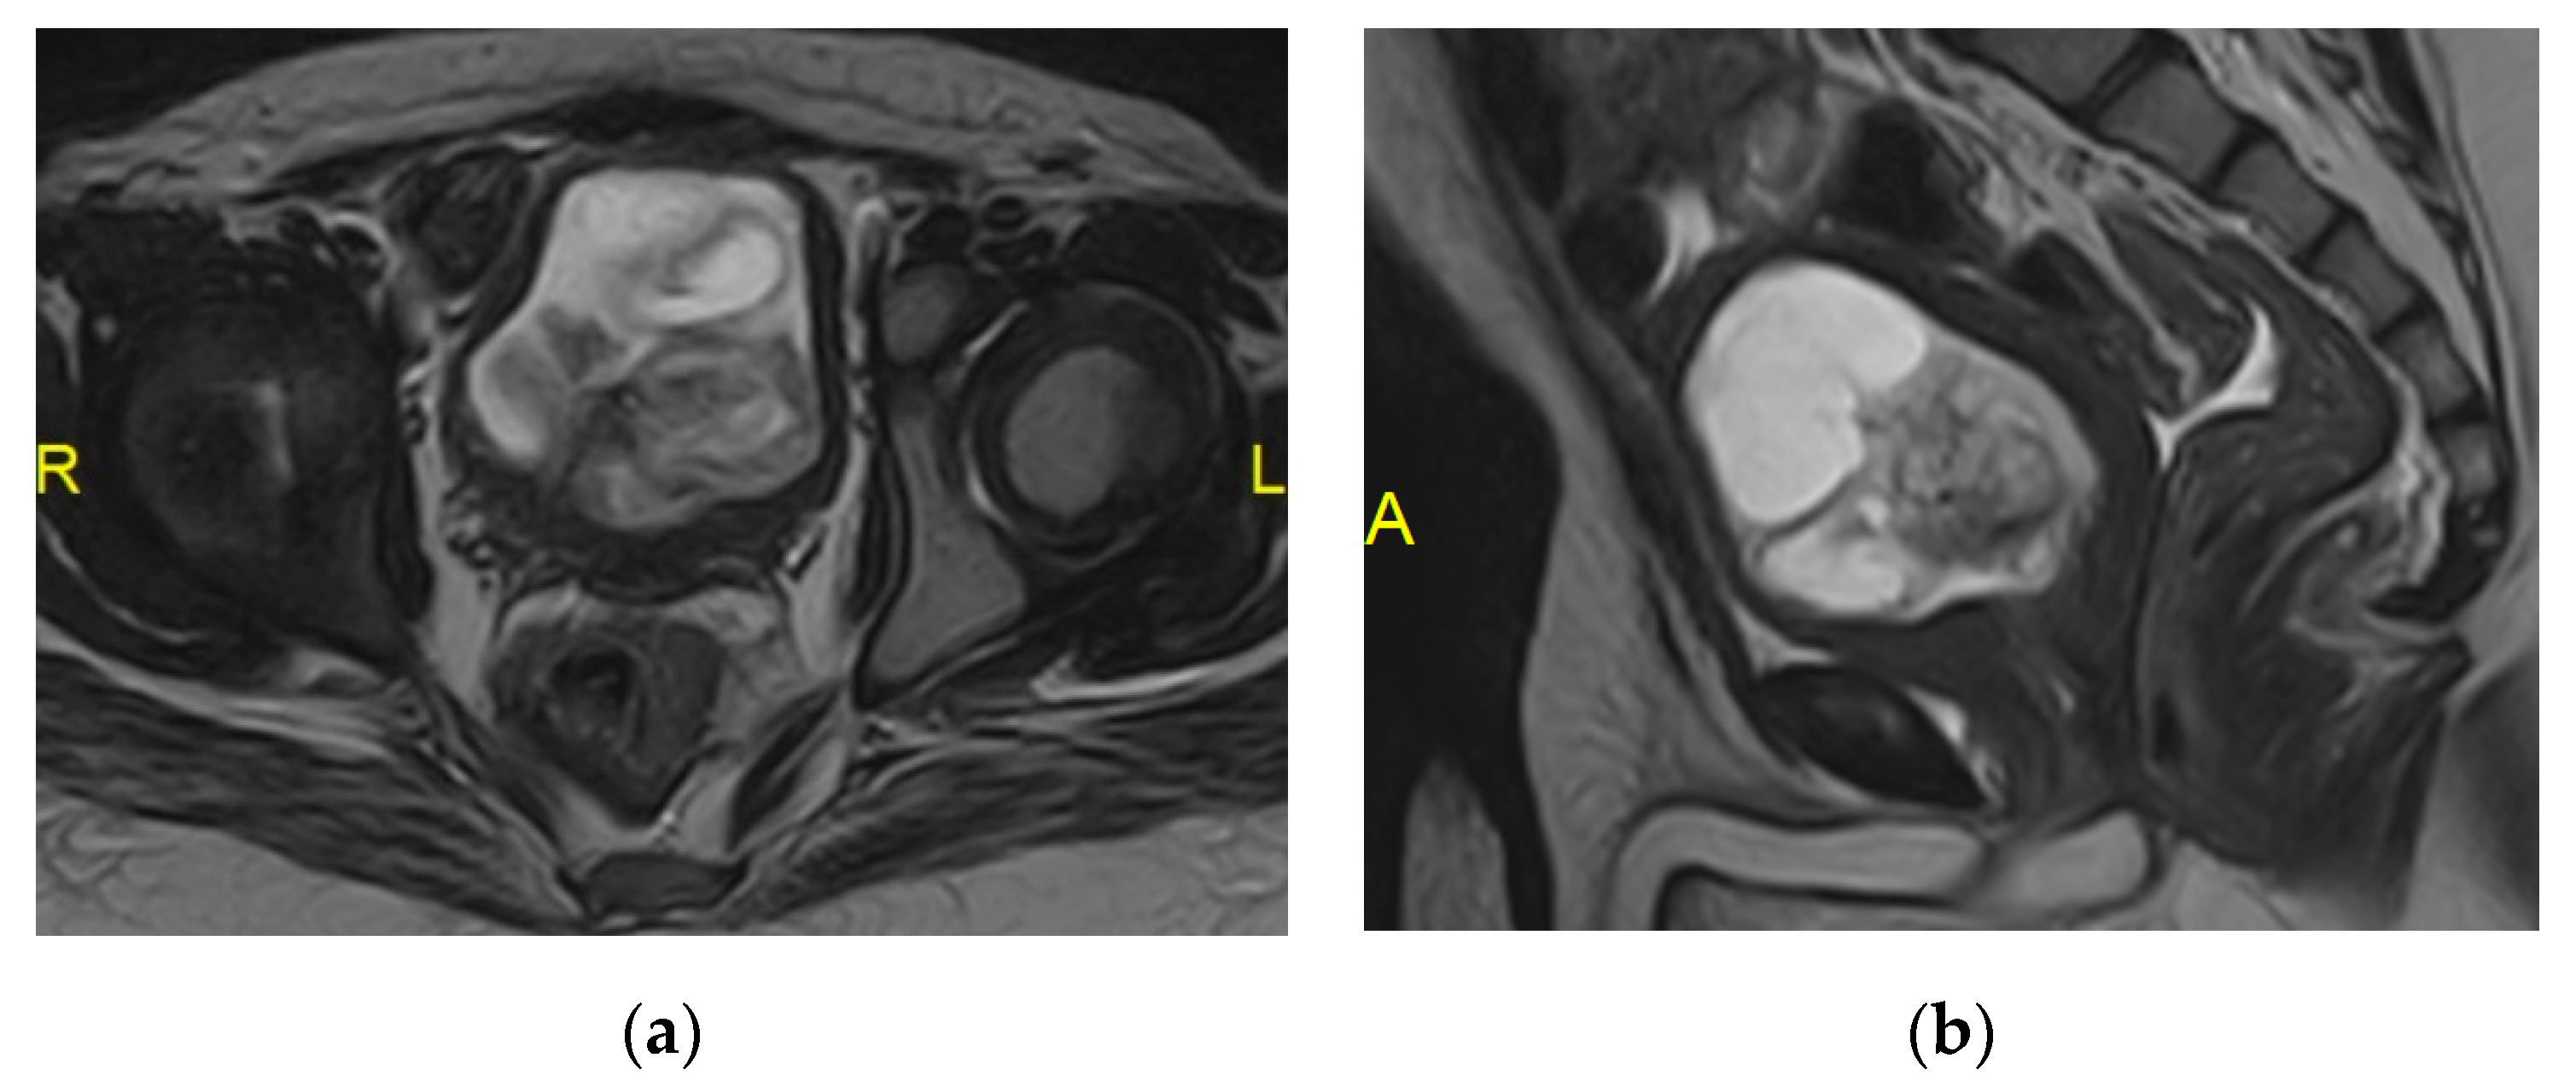

2.15. Acute Bacterial Prostatitis and Prostatic Abscess

| Prostatic abscess | Non enhancing fluid collection with peripheral or septal enhancement and non-enhancing central fluid. Possible extraprostatic extension |